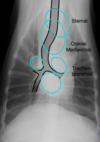

what is found in the cranioventral mediastinum

A

sternal lymph nodes

+/- thymus

8

Q

what is found in the craniodorsal mediastinum

Great vessels

 Trachea

 Esophagus

 Cranial mediastinal lymph nodes